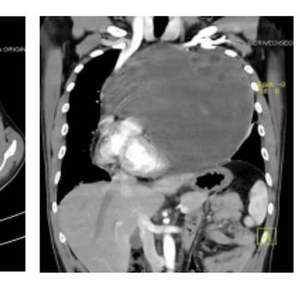

近日,四川大学华西医院肺癌中心周清华教授团队克服重重挑战,通过5个小时手术,为一例纵隔肿瘤压迫心脏、侵犯心包,伴肺功能极重度受损的29岁男性患者,成功摘除重达8.7kg、接近足球直径大小的罕见巨大恶性肿瘤。

因为想取出一颗大个头的纵隔生殖细胞瘤,术中保证患者生命体征稳定、完整切除肿瘤和受侵的组织器官,同时保证肿瘤不复发、患者术后器官各项功能可正常恢复,单是手术过程就十分复杂了,需要主刀医生具有非常强的传统外科手术技术。本次周清华教授救治这位病人时就在短短5小时内实施了纵隔肿瘤切除、部分心包切除术、心包补片修补重建、左肺上叶前段切除术、左肺上叶下舌段切除术五项操作。

针对纵隔生殖细胞瘤这类疾病,目前主要措施就是利用胸部增强CT早期诊断,一旦确诊就立即进行治疗,包括根据肿瘤大小、部位,对邻近组织器官侵犯、推移压迫情况不同,采取直接手术或先辅助化疗、放疗等措施后再手术,并没有有效的预防方法。